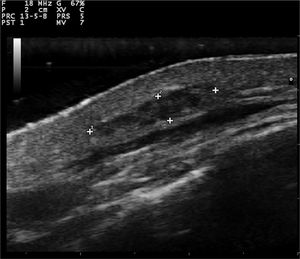

Gray-scale and color Doppler US examinations of both the subcutaneous nodule and one of the papules located on the right periareolar region (Fig. 1) were performed with a MyLab25Gold scanner equipped with a 10–18 MHz linear array transducer (Esaote, Genoa, Italy). High-frequency US of the subcutaneous malar nodule revealed an ill-defined, elongated, heterogeneous, and hypoechoic mass located in the deep dermis and hypodermis (Fig. 2). On the other hand, the US of the right periareolar papule showed a well-defined, round, homogeneous, and hypoechoic lesion located in the superficial dermis with an elevation of the epidermis (Fig. 3). Color and directional power Doppler US showed no increased vascularity in neither of the two lesions. Surgical removal and histopathology of two papules on the trunk confirmed the diagnosis of cutaneous myxomas (Fig. 4). The malar lesion was not excised for cosmetic reasons.

While cardiac myxomas sonographically present as pedunculated, atrial, hyperechoic masses; ultrasonography of cutaneous myxomas is yet to be described in the literature. The authors have observed that they show different ecographic features depending on their location in the skin. Superficial myxomas present as well-defined, round, homogeneous, and hypoechoic lesions located in the superficial dermis with an elevation of the epidermis. Instead, subcutaneous myxomas appear as ill-defined, elongated, heterogeneous and hypoechoic masses located in the deep dermis and hypodermis. The sonographic differential diagnosis of superficial myxomas should be made with benign skin tumors such as cysts, dermatofibromas, pilomatrixomas, and neurofibromas. Cysts are well-defined, round, hypoechoic, or anechoic lesions and usually present posterior enhancement and bilateral edge shadowing. Dermatofibromas are ill-defined, hypoechoic and heterogeneous lesions. In the US, pilomatrixomas appear as hypoechoic lesions with well-defined margins and typically present multiple small calcifications and posterior shadowing. Color Doppler US generally reveals a single artery that penetrates the lesion and gives rise to multiple intralesional branches.7 Neurofibromas are round, oval-shaped, or fusiform hypoechoic lesions that can show a connection with hypoechoic neural tracts. On the other hand, the sonographic differential diagnosis of subcutaneous myxomas should be made with deeper lesions like abscesses or lipomas. In the US, abscesses appear as heterogeneous fluid collections with irregular margins and increased vascular flow on Color Doppler US in case of active inflammation. Lipomas are usually ovoid, hypoechoic, subcutaneous masses with linear hyperechoic horizontal lines within the lesion.